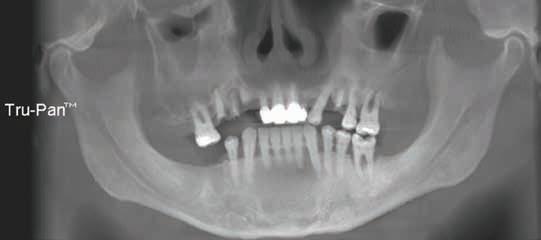

506 Oral and Maxillofacial Pathology: Case of the Month

509 Oral and Maxillofacial Pathology: Case of the Month Diagnosis and Management